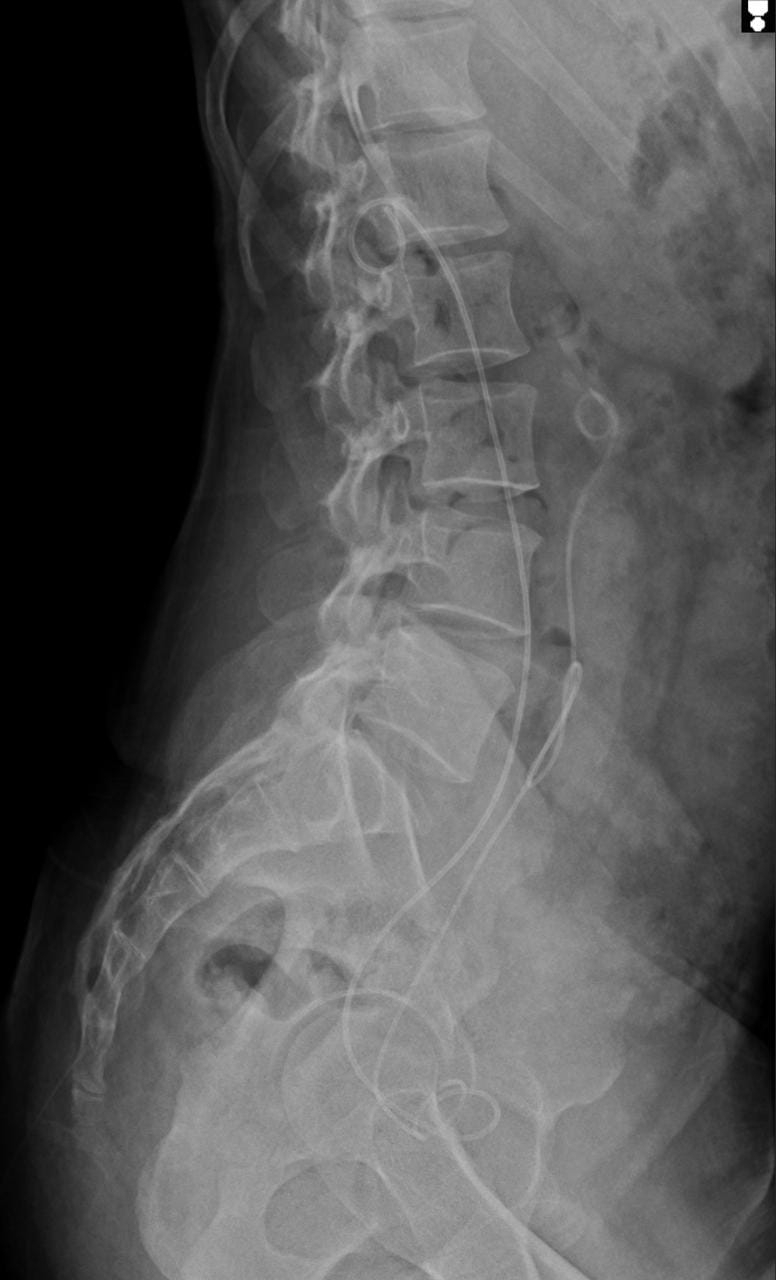

Multiple renal calculi largest measuring 13mm in right and 10 mm in left with B/L hydrouretronephrosis, Obstructive uropathy with tenia corposis et crusis with h/o Hypertension and Diabetes mellitus with left hip pain under evaluation